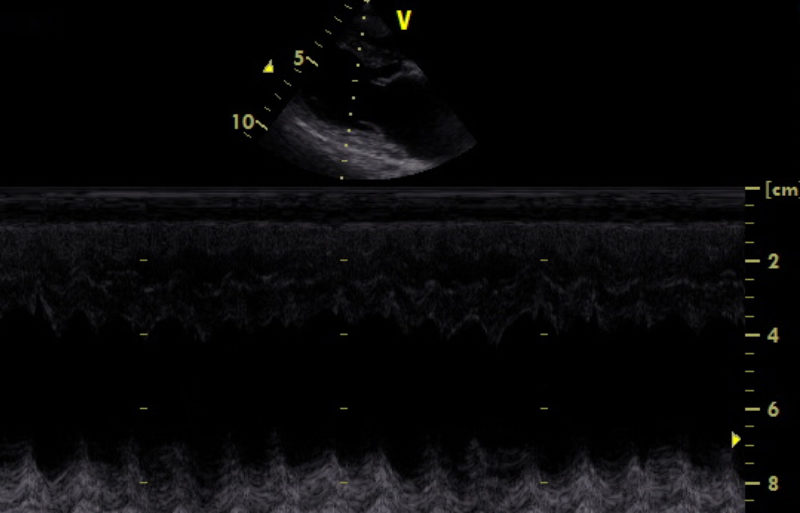

Es gibt verschiedene Ursachen für diese Form der Arrhythmie, welche mit Hilfe einer Echokardiographie weiter abgeklärt werden können. Daher wurde dem Besitzer als nächster diagnostischer Schritt ein Herzultraschall angeraten. Hierfür liegt der Hund auf einem speziellen Tisch und wird in rechter und linker Seitenlage geschallt. Im Herzultraschall zeigte sich in den Phasen, in denen „Astor“ die Rhythmusstörung hatte, eine stark verminderte Pumpleistung des linken Ventrikels mit einem subjektiv vergrößerten linken Herz (Hauptkammer und Vorkammer). Was sich dann auch in den Messwerten bestätigte. In Phasen, in denen der Herzschlag einen normalen Rhythmus hatte, war die Pumpleistung etwas besser, die Messwerte lagen im Graubereich. Der linke Vorhof war leicht vergrößert. Neoplasien oder Veränderungen im Herzmuskel konnten nicht dargestellt werden.